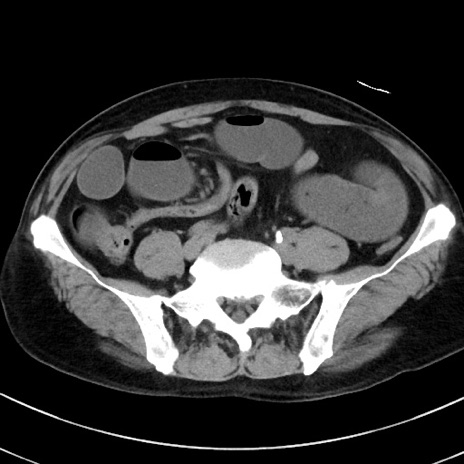

症例38(横断像)

【症例】70歳代 男性

【主訴】腹痛・嘔吐

【現病歴】昨晩より、嘔吐・腹痛あり。今朝になっても嘔吐あり。来院。

【既往歴】心臓バイパス手術、開腹胆摘、腸閉塞

【身体所見】BP 107/71mmHg、HR 116/min、腹部:平坦、軟、下腹部に軽度圧痛あり。反跳痛なし。

【データ】WBC 15100、CRP 0.32

冠状断像